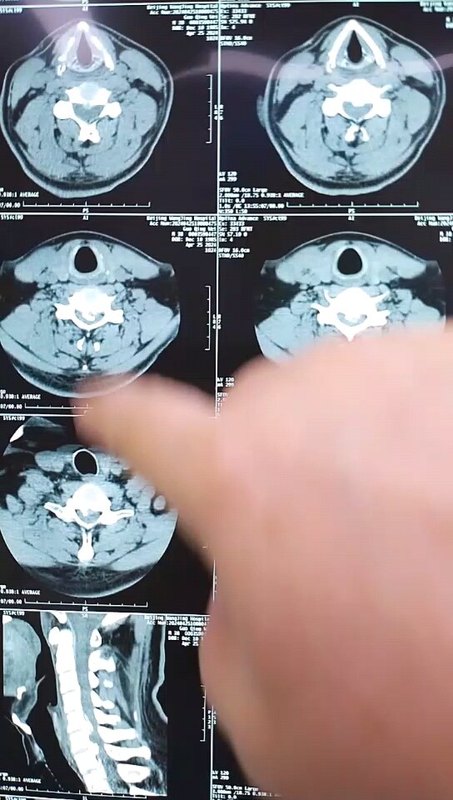

不少患者查出頸椎病后,發(fā)現(xiàn)不是頸椎受壓就是脊髓受壓,這兩種情況有什么不同呢?哪一種更嚴(yán)重呢?如果既壓迫到神經(jīng),又壓迫到脊髓,又該怎么辦呢?頸椎病壓到神經(jīng)和脊髓,有什么不同?事實上,這個問題是在對比神經(jīng)根型頸椎病和脊髓型頸椎病。頸椎病由于頸椎退化等各種原因?qū)е轮車纳窠?jīng)根、脊髓、血管等組織受壓,導(dǎo)致出現(xiàn)一系列癥狀。根據(jù)受壓組織不同,頸椎病又分為許多類型,其中最常見的就是神經(jīng)根型頸椎病,最嚴(yán)重的就是脊髓型頸椎病。顧名思義,神經(jīng)根型頸椎病常由于頸椎間盤突出等原因?qū)е律窠?jīng)根受壓,患者常會出現(xiàn)上肢的放射性疼痛、麻木、無力等癥狀;而脊髓型頸椎病壓迫到脊髓,患者除了上肢癥狀外,還會出現(xiàn)下肢的走路踩棉花感、走路不穩(wěn)等情況。這兩種類型的頸椎病治療方案也略有不同,神經(jīng)根型頸椎病多數(shù)情況下保守治療就可以了,只有患者的病情嚴(yán)重,保守治療無效,嚴(yán)重影響生活了才會考慮手術(shù)干預(yù)。但脊髓型頸椎病是一旦確診就需要盡快手術(shù)的,保守治療效果不好,而且脊髓長時間受壓,可能會導(dǎo)致一些不可逆的功能障礙。既壓到神經(jīng),又壓到脊髓,這種頸椎病要怎么辦?最近,宣武醫(yī)院王作偉主任接診了一位44歲的女性頸椎病患者。這位患者出現(xiàn)脖子疼痛、僵硬已經(jīng)有3年了,難受的時候會做熱敷、針灸,但在2個月前,她的右側(cè)上肢出現(xiàn)了放射性疼痛,麻木乏力,偶爾時不時還會出現(xiàn)走路腳底有踩棉感,這讓她非常難受,去了當(dāng)?shù)蒯t(yī)院檢查出頸椎病?;颊邽榱诉M(jìn)一步治療,最后找到王主任。從她的片子、查體等檢查結(jié)果上看,她的頸椎生理曲度消失,甚至有點反弓,而且在頸4-7多個節(jié)段出現(xiàn)了椎間盤突出,突出不僅壓迫到了神經(jīng)根,同時也壓迫到了脊髓。這種情況該怎么辦?這樣的情況,王主任建議進(jìn)行手術(shù)治療。兩者都受到壓迫,尤其是她出現(xiàn)脊髓受壓,并出現(xiàn)下肢走路問題,這時保守治療已經(jīng)沒有太大效果,這種情況還是要盡快手術(shù)處理。術(shù)前影像學(xué)資料:在獲得患者和家屬的同意后,王主任為她成功進(jìn)行了手術(shù)治療。手術(shù)對突出的椎間盤進(jìn)行了切除,給神經(jīng)根和脊髓進(jìn)行了徹底減壓,并給頸椎進(jìn)行內(nèi)固定,重建了穩(wěn)定性。術(shù)后,患者的上肢疼痛立馬得到極大緩解,不到第3天,她就已經(jīng)可以戴著頸托獨自行走了,其余的麻木、乏力癥狀也在逐漸好轉(zhuǎn)。術(shù)后影像學(xué)資料:最后,不管您是神經(jīng)根受壓、脊髓受壓,還是兩個都受壓,出現(xiàn)類似上面這些癥狀時,都要及時去醫(yī)院檢查。若單純是神經(jīng)根型頸椎病,對生活影響不大,建議您先保守治療;若是壓到脊髓或兩個都壓到了,就要考慮盡快手術(shù)干預(yù)了。